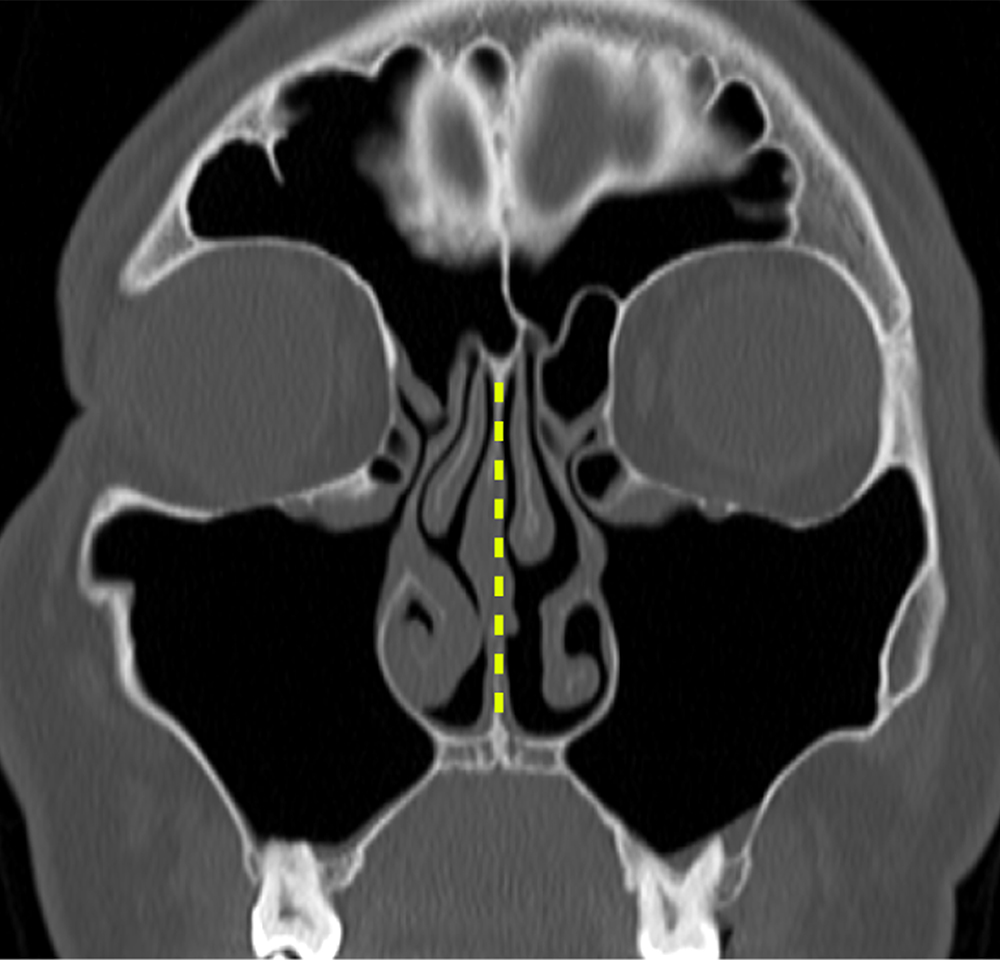

비중격 교정술

코 안쪽의 휘어진 연골이나 뼈를 교정하거나

돌출된 부분을 절제하여

코막힘을 해소하는 수술입니다.

이 수술은 코 안쪽으로 진행되므로

겉으로 보이는 흉터가 없으며,

약물 치료 등 보존적인 방법으로

증상이 개선되지 않을 때 고려됩니다.

수술 전

수술 후

비중격 교정술은 콧구멍 안쪽으로 수술이

이루어져 겉으로 보이는 상처나 흉터가 없으며,

코 본연의 기능을 회복하는 데 중점을 둡니다.

삼성 진 이비인후과에서는 개인의 비중격 만곡

정도와 코 내부 구조에 맞춰 가장 안전하고

효과적인 수술 방법을 적용합니다.